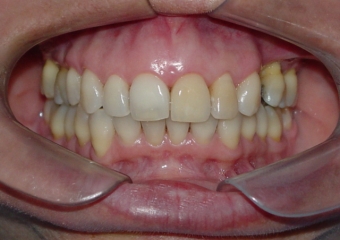

Imagens iniciais, observando a ausência do pré molar superior